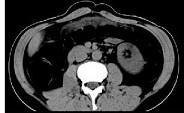

问题 女,51岁,腹胀、腹痛、进行性消瘦,影像检查如下图,最佳诊断是 ( )

选项 A.乙状结肠Crohn病 B.乙状结肠结核 C.乙状结肠癌 D.乙状结肠淋巴瘤 E.乙状结肠息肉

答案 C